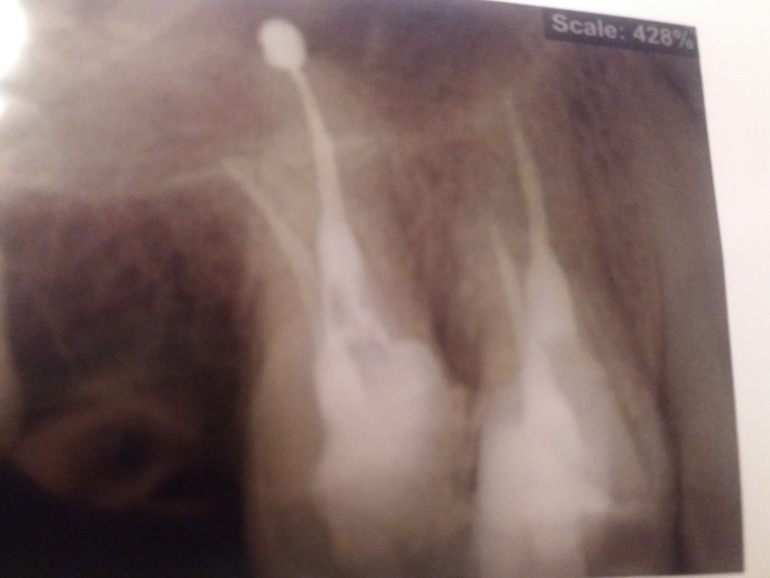

Сегодня плобировали каналы. После сделала снимок. Материал выведен за пределы корня. Чем это черевато? Мой врач увидит снимок только через неделю. Нужно ли срочно показать ей? Снимок прилагаю

Да, лучше показать снимок своему стоматологу, т.к. еще можно с меньшими усилиями перепломбировать соседние каналы, которые заполнены не полностью.

Не знаем, какрй пастой пломбировались зуюы. Есть те, что со временем рассасываются, если их вывести за верхушку. И даже оказывая терапевтический эффект.

Есть не рассасывающиеся, но:

- они могут не давать о себе знать никогда.

- а могут вызвать воспаление.

Все зависит от Вашего иммунитета.

Но зубы перелечить нужно. Каналы не полностью заполнены